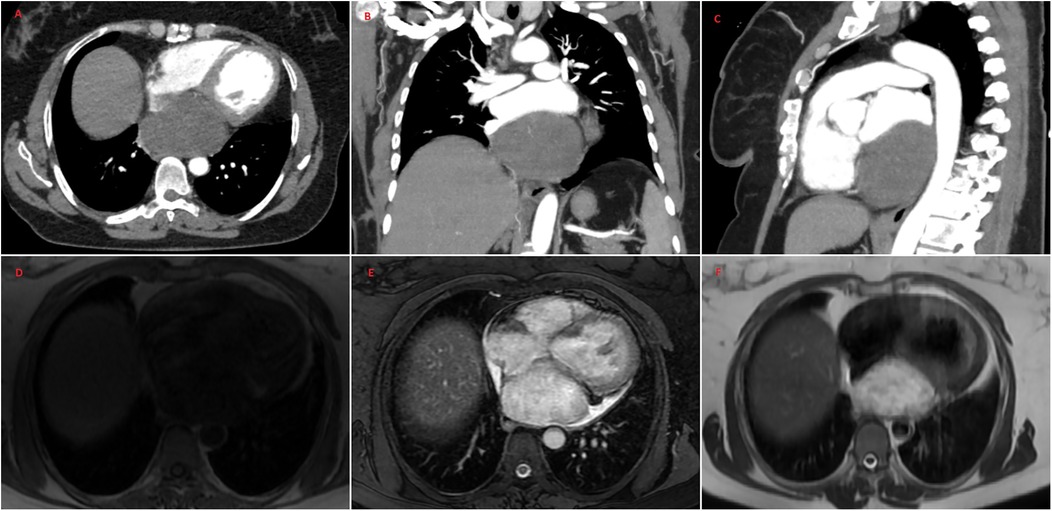

A 47-year-old female patient applied to the cardiology outpatient clinic with complaints of exertional dyspnea and intermittent chest pain. The patient's New York Heart Association (NYHA) functional capacity score was 2–3. Chest pain was unrelated to exertion. The patient had hypertension and was normotensive under perindopril 10 mg and amlodipine 10 mg treatments. She was a nonsmoker and had Class I obesity with a body mass index of 30.8 kg/m2. Physical examination was normal. Laboratory parameters showed an elevation of low-density lipoprotein at 187 mg/dl and an elevation of N-terminus pro-B-type natriuretic peptide (NT-proBNP) at 684 pg/ml. The electrocardiogram showed sinus rhythm with a rate of 83 bpm and no abnormalities. Transthoracic echocardiography (TTE) revealed a well-circumscribed hypoechoic mass lesion measuring 8.5 cm × 5.4 cm, located behind the posterior walls of the left atrium and left ventricle, causing significant compression of the left atrium (Figures 1A,B). Other findings of TTE were; normal left ventricular systolic function with a left ventricular ejection fraction (LVEF) of 65%, mild dilatation of the left atrium with a left atrial volume index (LAVI) of 36 ml/m2, mild mitral valve regurgitation, mild tricuspid valve regurgitation, tricuspid valve regurgitation velocity 3.2 m/s, grade II diastolic dysfunction and normal right ventricular systolic function with a tricuspid annular plane systolic excursion of 22 mm. Transesophageal echocardiography (TEE) was performed for detailed evaluation of the mass and its neighbors. TEE showed a mass containing a cystic lesion that caused significant compression of the left atrium (LA) and mild compression of the inferior vena cava (IVC) (Figure 2). No pulmonary venous return anomaly or obvious compression of the pulmonary veins was detected on TEE. Thoracic computed tomography (CT) angiography revealed a pericardial mass lesion measuring 10.1 cm × 8.1 cm × 5.2 cm in size, with regular borders and soft tissue density, located in the posterior mediastinum, adjacent to the LA and descending aorta, creating significant compression on the esophagus (Figure 3). The whole-body 18F-fluorodeoxyglucose (18F-FDG) positron emission tomography (PET)-CT images revealed a giant pericardial mass with mild to moderate 18F-FDG avidity (Figure 4). No metastatic lesions were detected. Magnetic resonance imaging (MRI) showed a well circumscribed, T1-hypointense and T2-hyperintense pericardial mass. The mass was observed to have homogeneous signal intensity on T1 and T2-weighted images. There was no direct myocardial infiltration and/or left atrial invasion (Figure 3). Contrast-enhanced images were not obtained for the patient who had a history of anaphylactic shock due to a gadolinium-based contrast agent. CT and MRI showed that the mass did not cause myocardial involvement, however, the mass could not be demarcated from the LA and IVC. The coronary angiogram did not detect obstructive coronary artery disease or coronary artery compression due to the mass. For the histological diagnosis of this giant pericardial mass, EUS-FNA was performed. Histological evaluation revealed foci of spindle cell proliferation forming Antoni A and Antoni B areas. Immunohistochemical studies revealed that these spindle cells stained diffusely positive for S100, which was consistent with schwannoma. The Ki-67 index was less than 1%.

Figure 3

Figure 3. Thoracic CT angiography (A–C) and MRI (D–F) images of the patient. CT and MRI show a well-circumscribed pericardial mass measuring 10.1 cm × 8.1 cm × 5.2 cm located in the posterior mediastinum. CT and MRI demonstrated no evidence of the invasion of the inferior vena cava, left atrium, left ventricle and pulmonary veins. MRI showed that the mass was T1-hypointense (D) and T2-hyperintense (F) The mass was observed to have homogeneous signal intensity on T1 and T2-weighted images (D–F) The mass showed high signal intensity on T2-weighted fat suppression sequence (E) CT, computed tomography; MRI, magnetic resonance imaging.